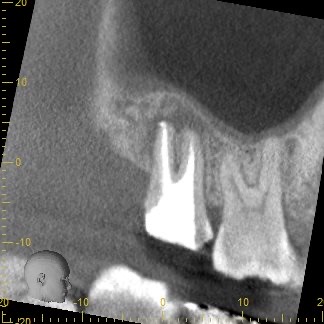

3ヶ月経過後のCT画像です。

術前のCT画像と比較すると、歯根周囲の黒くなっていた部分の骨の回復を認めました😊

ここまで回復すれば長期的な安定期が期待できるため、被せ物を作製していきます。